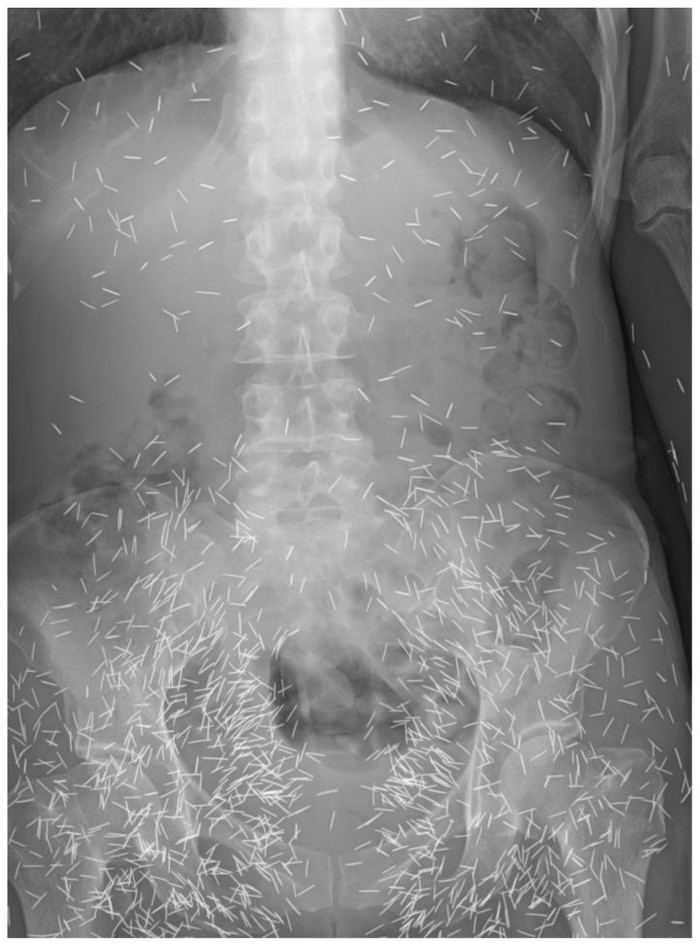

Penampakan X-ray seorang wanita di Malaysia yang mengeluh sakit perut nyeri perut kronis. Setelah diperiksa, ternyata ada banyak jarum di tubuhnya. (Foto: Journal of Radiology Case Reports)

Diprediksi ada sekitar 800 jarum 'susuk' yang bersarang di tubuh wanita ini. Radiografi perut dari pasien yang sama menunjukkan jarum berada paling banyak di area panggul. (Foto: Journal of Radiology Case Reports)